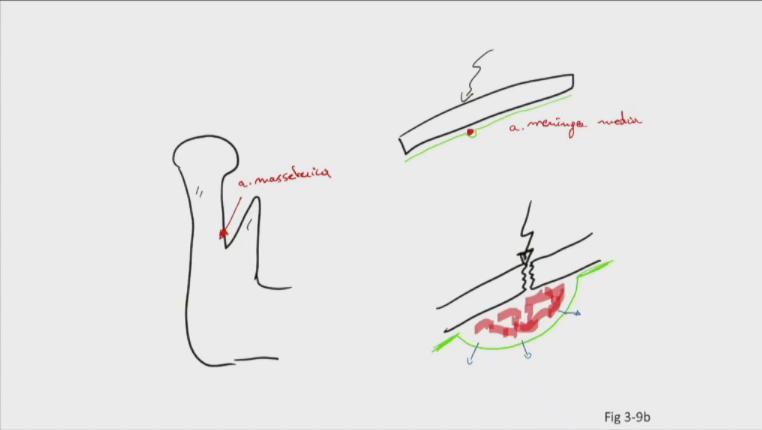

Fig 3.09b

A detail a. masseterica

proc. condylaris proc. coronoideus a masseterica

B detail a. meningea media

schedel dura mater (groen) a meningea media

C trauma

schedelfractuur epiduraal haematoom druk op hersenen stijgt